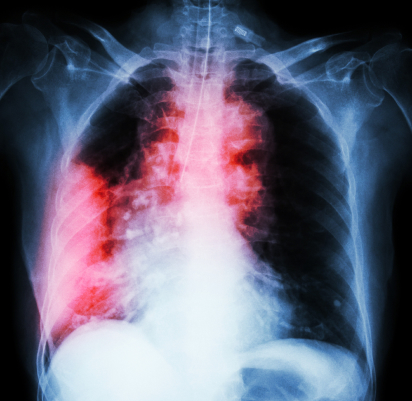

Компьютерная и магнитно-резонансная томографии выполняются аппаратами фирмы Siemens. Томографы экспертного класса выявляют малейшие сосудистые патологии и новообразования на начальных стадиях развития. Снимки, сделанные подобной техникой, отличаются высокой точностью и ясностью.